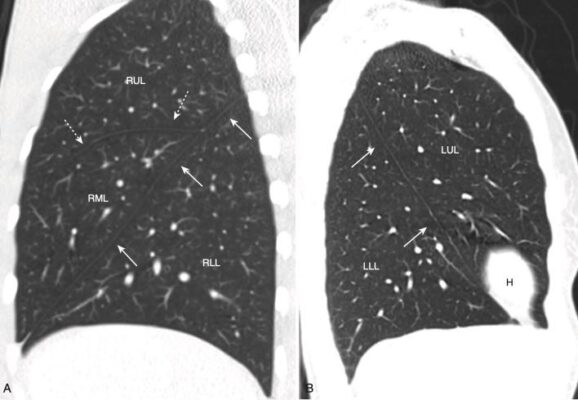

- Tất cả các giải phẫu có thể nhìn thấy trên phim X quang ngực thông thường đều quan sát được trên phim chụp CT ngực, nhưng với độ chi tiết hơn. Với việc tái tạo các hình ảnh CT lát cắt mỏng, phổi có thể được hình dung ở bất kỳ mặt phẳng nào, mặc dù ba mặt phẳng phổ biến nhất là mặt phẳng ngang (axial), mặt phẳng đứng dọc (sagittal) và mặt phẳng trán (coronal, còn gọi là mặt phẳng vành) (Hình 11).

- Tùy thuộc vào độ dày của lát cắt, các rãnh sẽ có thể nhìn thấy dưới dạng các đường trắng mỏng hoặc bằng một dải vô mạch dày khoảng 2 cm khi chúng đi chéo qua phổi (Hình 16).

- Rãnh nhỏ đi cùng mặt phẳng ngang như với hình ảnh CT cắt ngang nên thường không thể nhìn thấy, ngoại trừ ở mặt phẳng đứng dọc hoặc mặt phẳng trán. Tuy nhiên, giống như các rãnh lớn, có thể suy luận ra vị trí của rãnh nhỏ bởi một vùng vô mạch giữa các thùy trên và thùy giữa phải (xem Hình 16, A).

- Rãnh lớn phân cách thuỳ trên với thuỳ thấp hơn. Ở bên phải, rãnh bé phân chia thùy giữa. Tương tự của nó ở bên trái là phân thuỳ lưỡi của thùy trên trái (Hình 17).